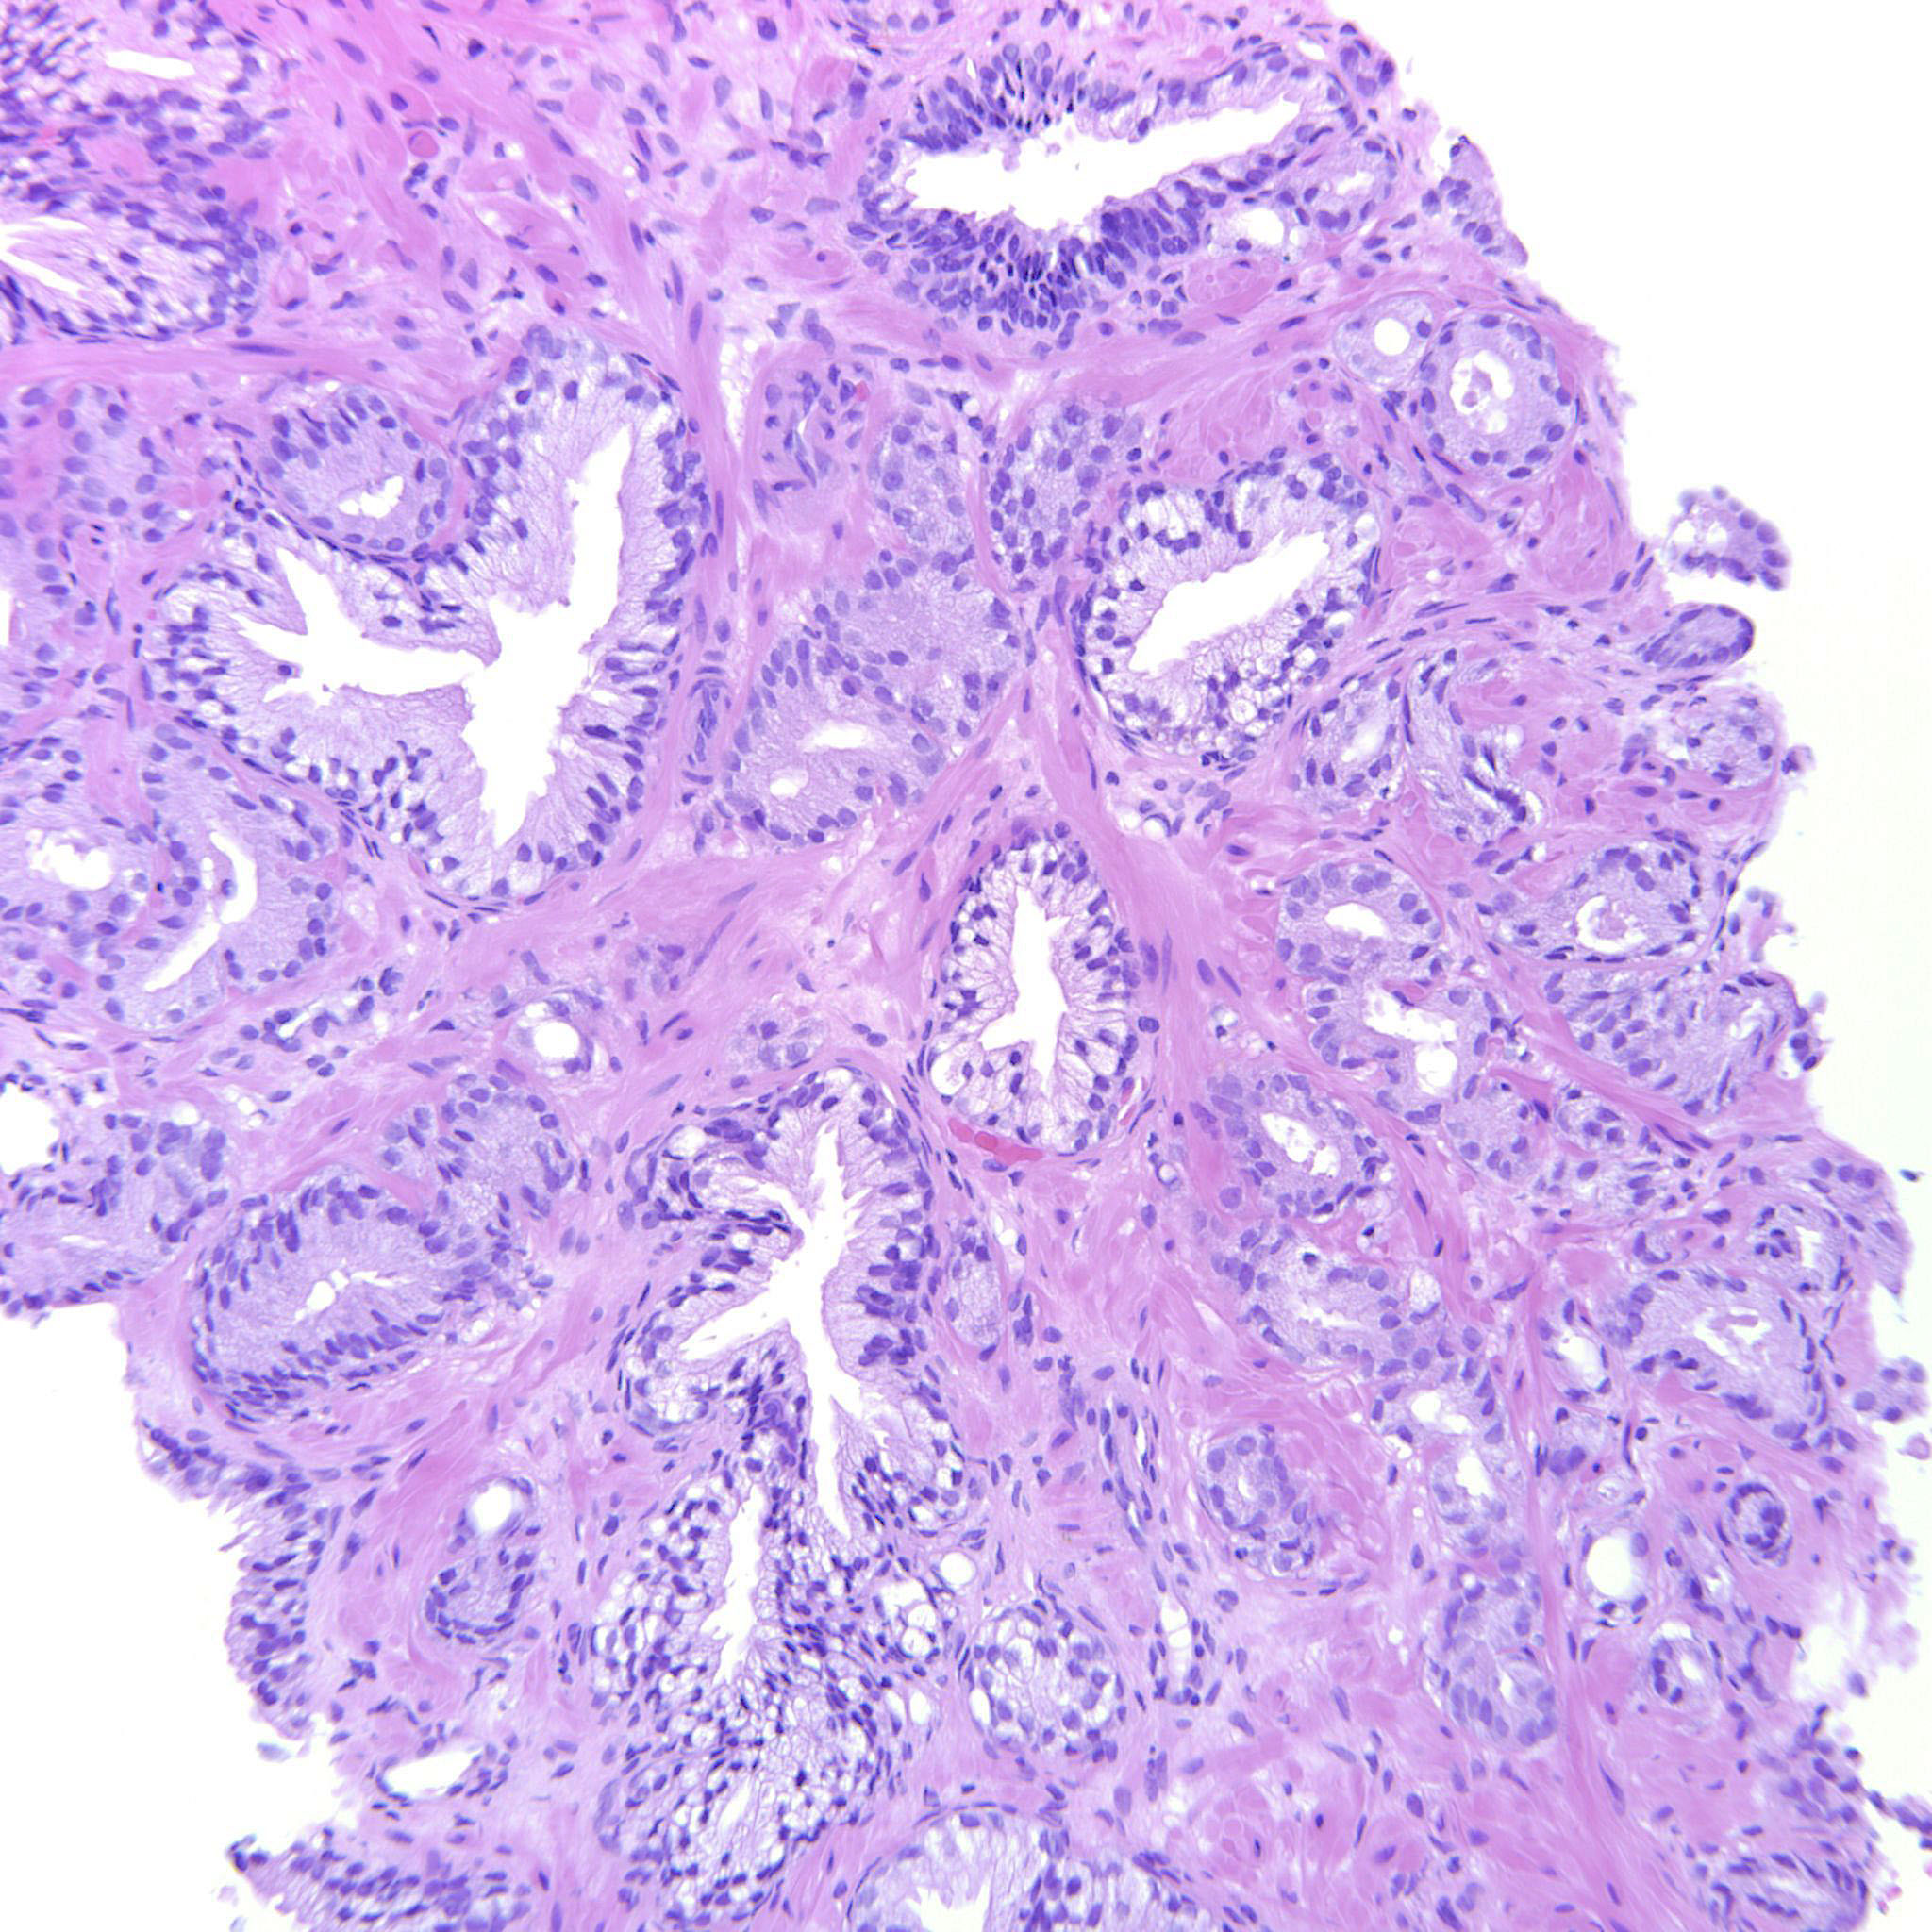

Prostate cancer grading

Case ID: 480